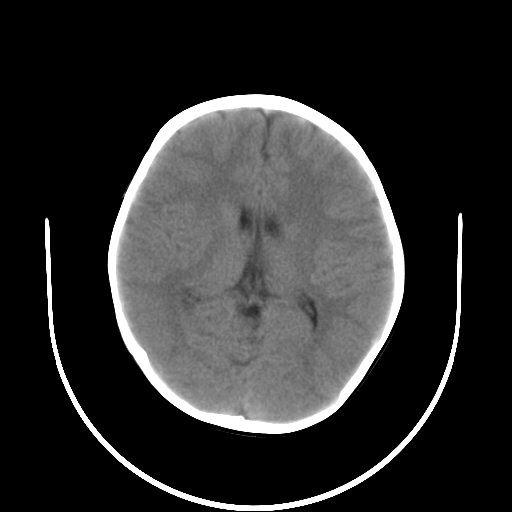

以下是引用深泽交通医院在2009-10-16 8:25:00的发言:[br]右眼环出血伴异物

以下是引用卜一在2009-10-16 15:01:00的发言:[br]右眼球挫裂伤伴异物!

以下是引用拾荒者在2009-10-17 18:38:00的发言:[br]鼻面部皮下积气,右侧睑缘及眼球壁高密度异物影,左侧眼球壁晶状体内侧缘处是圆形低密度影。低密度异物?应提请眼科医生注意。